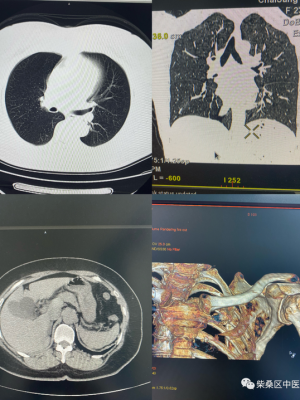

CT检查临床应用及图像表现

临床应用

①中枢部位神经系统疾病:颅内腹部肿瘤做、脓肿、寄生虫病、外伤性血肿与脑损伤、缺血与脑出血。

②框内占位性病变视频、鼻窦癌等。

③肺部腹部感染性视频疾病、肺癌视频和纵隔肿瘤少钱。

④生成立体三维图像,x光片检查费用是多少。

⑤肝、胆、腹腔及腹膜后间隙及肾上腺及泌尿生殖系统、肠道病变向腔外侵犯费用或远处转移等等,腹部x光片可以检查什么,x光片能检查什么。

图像表现